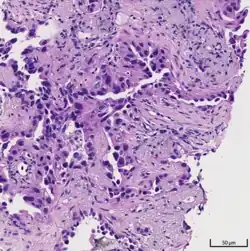

Histopathology

If possible, a biopsy of any suspected lung tumor is performed to make a microscopic evaluation of the cells involved and is ultimately required to confirm diagnosis.[7] Biopsy should be attempted in distant lesions first to establish a histologic diagnosis and to simultaneously confirm metastatic staging. The biopsy material is also used to analyze whether the tumor express any specific mutations suitable for targeted therapy (e.g. EGFR mutation or ALK mutation). Biopsy can be accomplished via bronchoscopy, transthoracic needle biopsy, and video-assisted thorascopic surgery (VATS).[4]

While sputum cytology has been shown to have limited utility, thoracentesis, or aspiration of pleural fluid with an ultrasound-guided needle, should be performed when pleural effusion is present. When malignant cells are identified in the pleural aspirate of patients highly suspect for lung cancer, a definitive diagnosis and staging (stage IV adenocarcinoma of the lung) is established.[4]

Adenocarcinoma of the lung tends to stain mucin positive as it is derived from the mucus-producing glands of the lungs. Similar to other adenocarcinoma, if this tumor is well differentiated (low grade) it will resemble the normal glandular structure. Poorly differentiated adenocarcinoma will not resemble the normal glands (high grade) and will be detected by seeing that they stain positive for mucin (which the glands produce). Adenocarcinoma can also be distinguished by staining for TTF-1, a cell marker for adenocarcinoma.[29]

As discussed previously, the category of adenocarcinoma includes are range of subtypes, and any one tumor tends to be heterogeneous in composition. Several major subtypes are currently recognized by the World Health Organization (WHO)[1] and the International Association for the Study of Lung Cancer (IASLC) / American Thoracic Society (ATS) / European Respiratory Society (ERS):[30][31][32] lepidic predominant adenocarcinoma, acinar predominant adenocarcinoma, papillary predominant adenocarcinoma, micropapillary predominant adenocarcinoma, solid predominant adenocarcinoma, and solid predominant with mucin production. In as many as 80% of these tumors, components of more than one subtype will be recognized. Surgically resected tumors should be classified by comprehensive histological subtyping, describing patterns of involvement in increments of 5%. The predominant histologic subtype is then used to classify the tumor overall.[2] The predominant subtype is prognostic for survival after complete resection.[33]

To reveal the adenocarcinomatous lineage of the solid variant, demonstration of intracellular mucin production may be performed. Foci of squamous metaplasia and dysplasia may be present in the epithelium proximal to adenocarcinomas, but these are not the precursor lesions for this tumor. Rather, the precursor of peripheral adenocarcinomas has been termed atypical adenomatous hyperplasia (AAH).[10] Microscopically, AAH is a well-demarcated focus of epithelial proliferation, containing cuboidal to low-columnar cells resembling club cells or type II pneumocytes.[10] These demonstrate various degrees of cytologic atypia, including hyperchromasia, pleomorphism, prominent nucleoli.[10] However, the atypia is not to the extent as seen in frank adenocarcinomas.[10] Lesions of AAH are monoclonal, and they share many of the molecular aberrations (like KRAS mutations) that are associated with adenocarcinomas.[10]